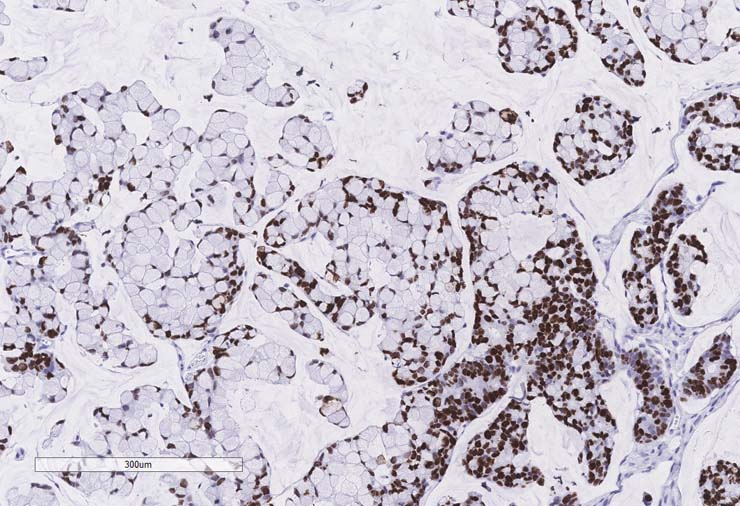

P0 tumor F240 for PDX model TM00351 stained for Ki67. Staining was positive.

P1 tumor F239 ID003 for PDX model TM00351 stained for Ki67. Staining was positive.

P2 tumor F239 ID011 for PDX model TM00351 stained for Ki67. Staining was positive.